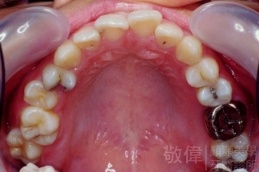

矯正前-上   矯正前-下

矯正後-上   矯正後-下

<個案說明>

上顎暴牙且牙齒極度混亂,經由矯正之後,臉型大幅度改善,牙齒的排列更加的整齊健康。相較於之前眼神充滿精神,自信心展現無遺。